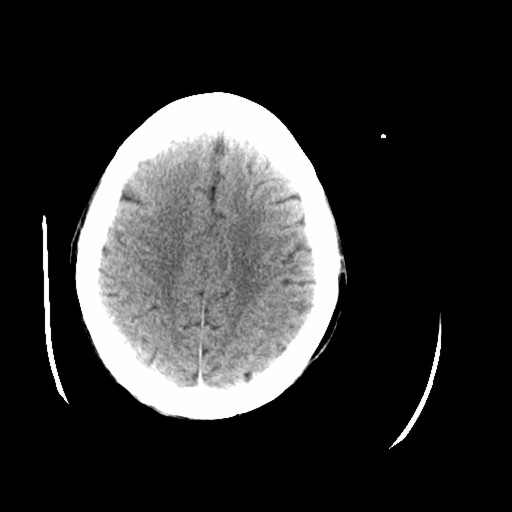

标题: CT16233:女,44岁,智障多年,现感头痛 [打印本页]

标题: CT16233:女,44岁,智障多年,现感头痛

小脑有啥病变?

老年脑,萎缩表现

脑萎缩

44岁  小脑表现为萎缩? 原因是什么呢?ct诊断上可报小脑萎缩吗?

橄榄桥小脑萎缩.左侧小脑脚腔梗.

为什么不考虑发育畸形呢

1)小脑萎缩。2)小脑蚓部发育不良。

橄榄桥小脑萎缩可能,建议mri进一步检查以进一步排查。

小脑萎缩征,原因待定.

橄榄桥小脑萎缩